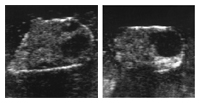

Der Gelbkörper (Corpus luteum) hat sich unter dem Einfluss von Prostaglandin F2alpha stark zurück gebildet. Ein dominantes Eibläschen (Graaf’scher Follikel) wächst heran. Es ist glatt und prall (uhrglasartig) und hat einen Durchmesser von gut 1cm.